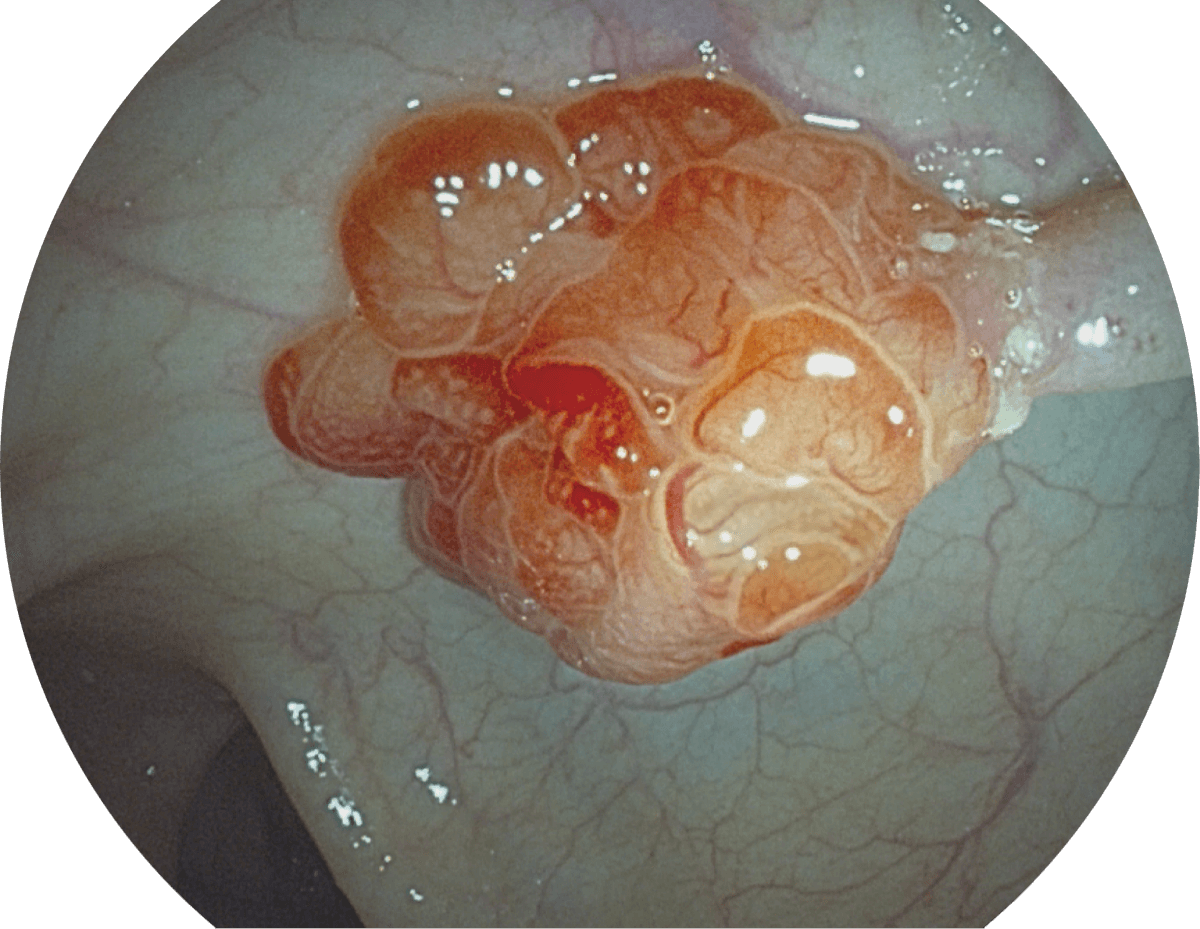

具有聚谱成像技术(SFI)及光电复合染色成像技术(VIST),可完美呈现粘膜细节及病变特征。

(Spectral Focused lmaging, SFI)

WL